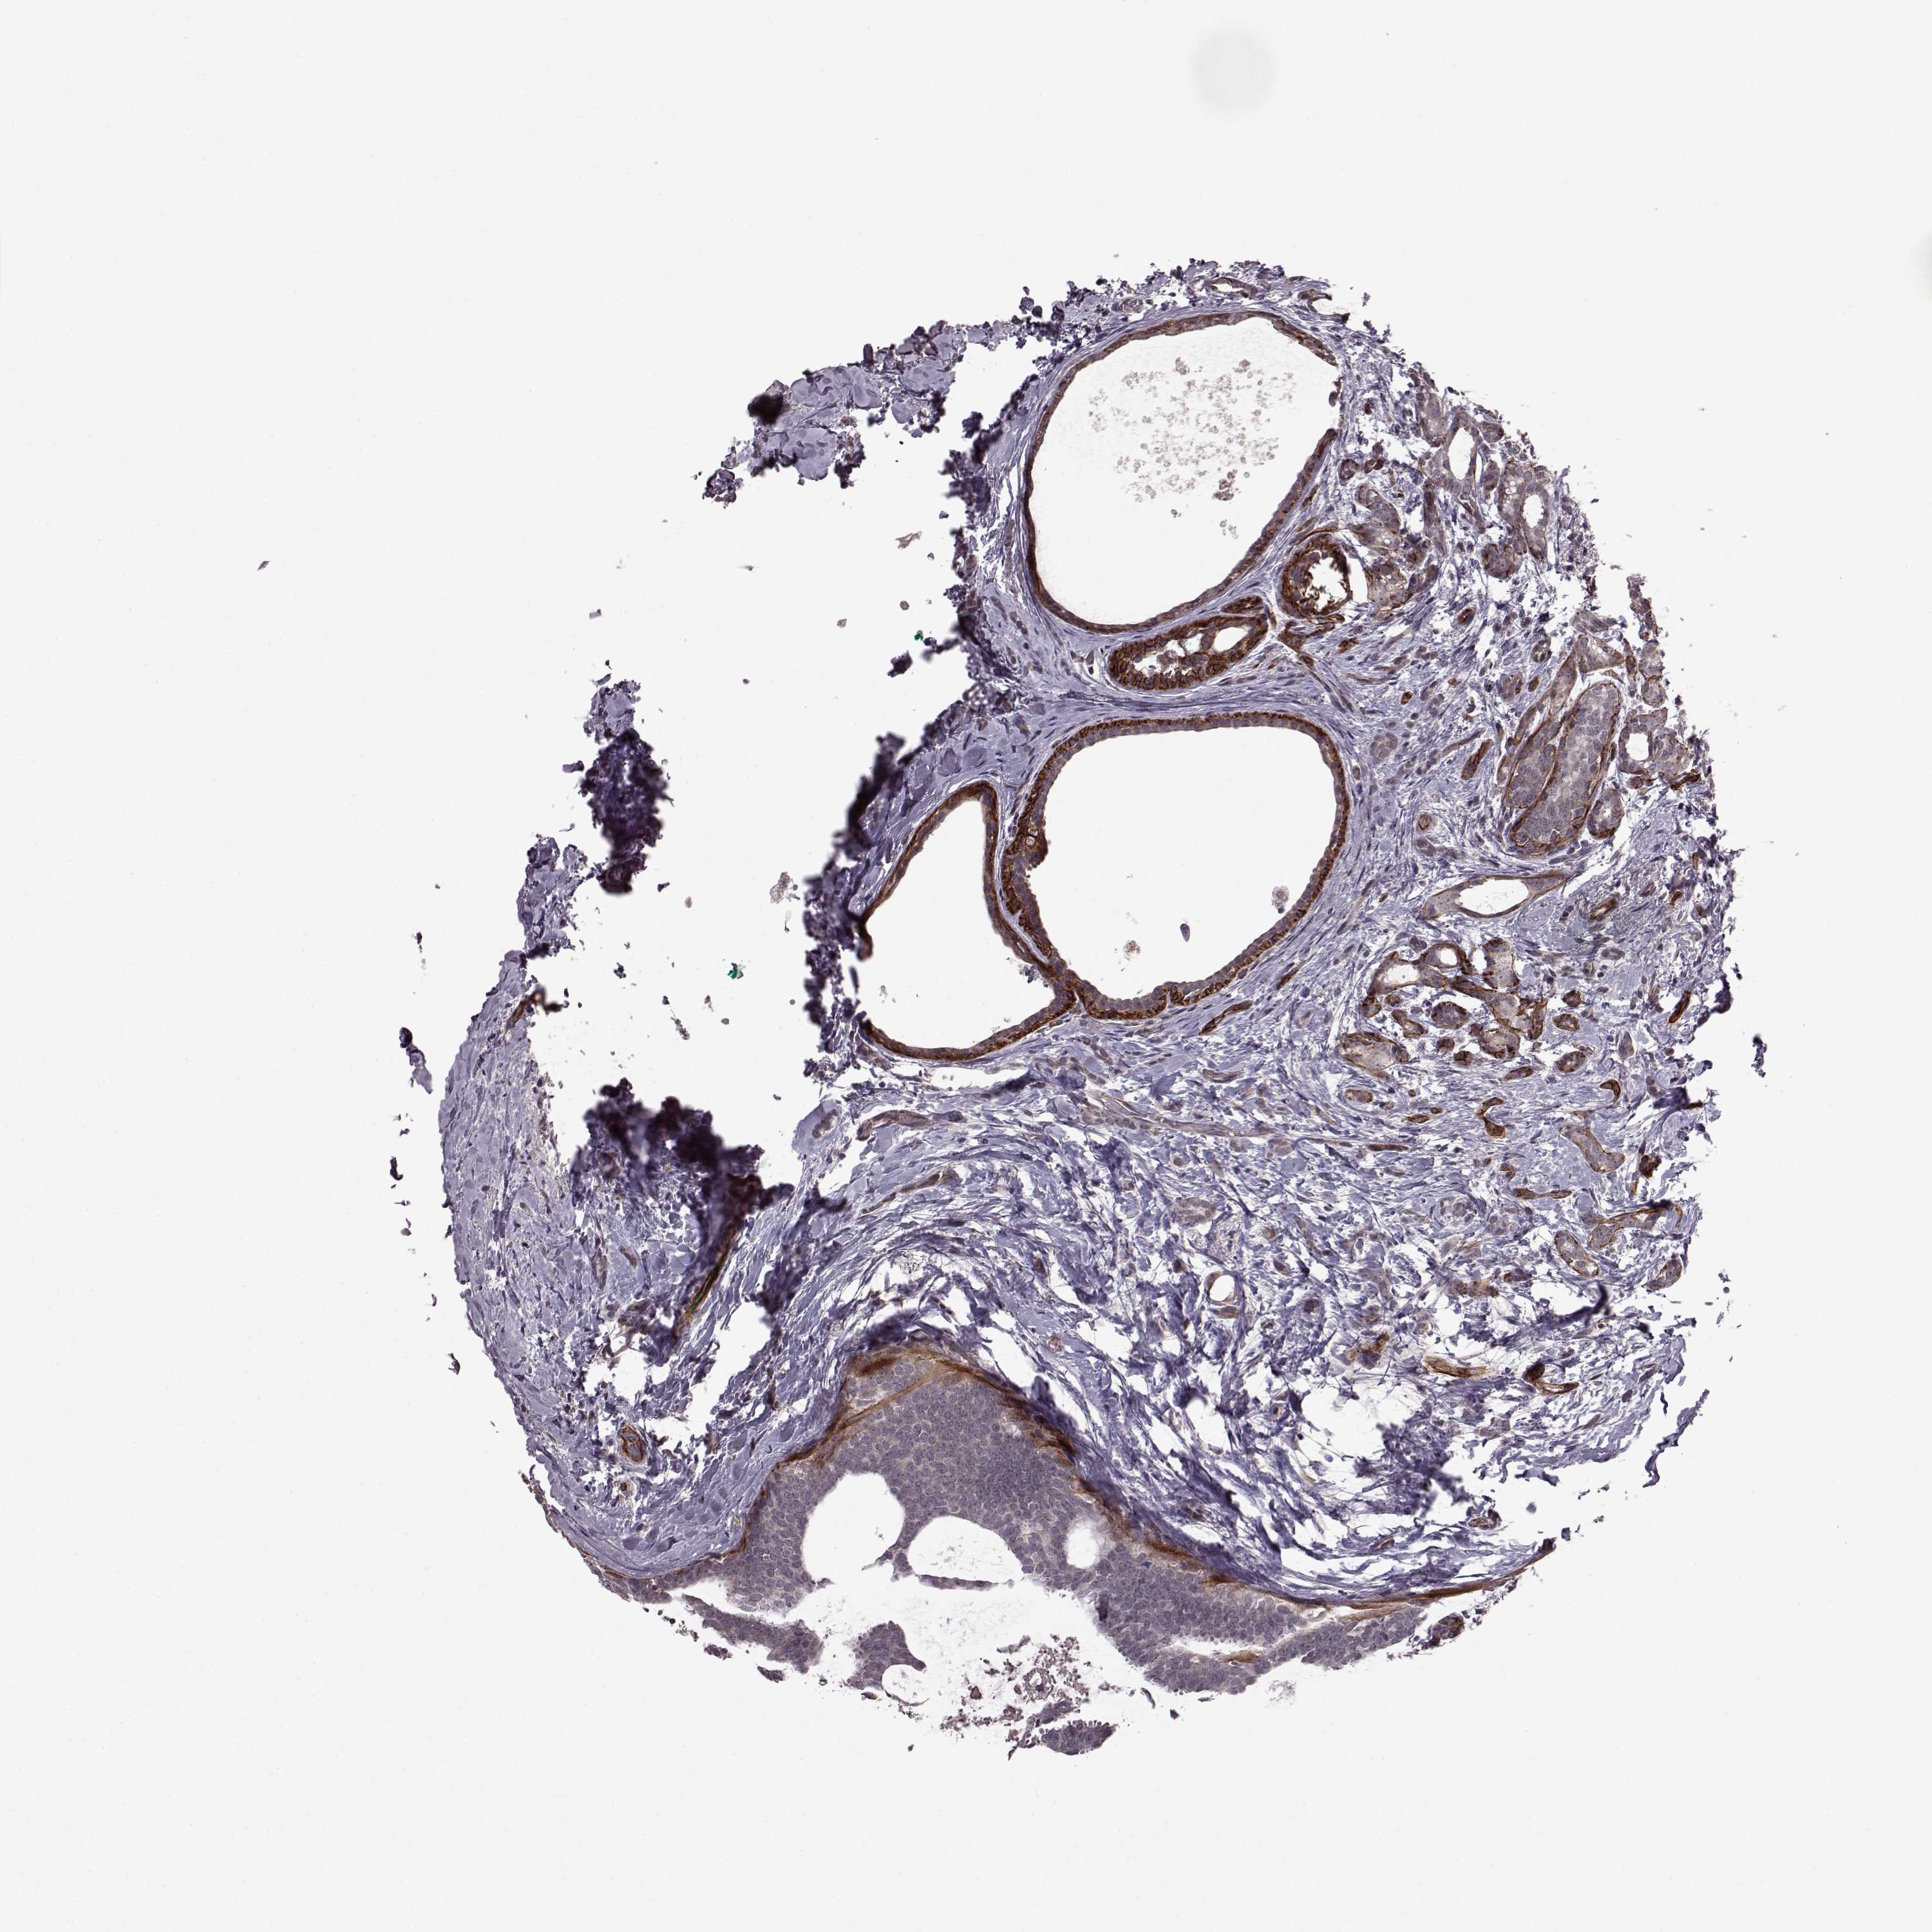

CANCER BREAST CANCER Show tissue menu

BRCA TCGA BRCA VALIDATION PROTEIN EXPRESSION